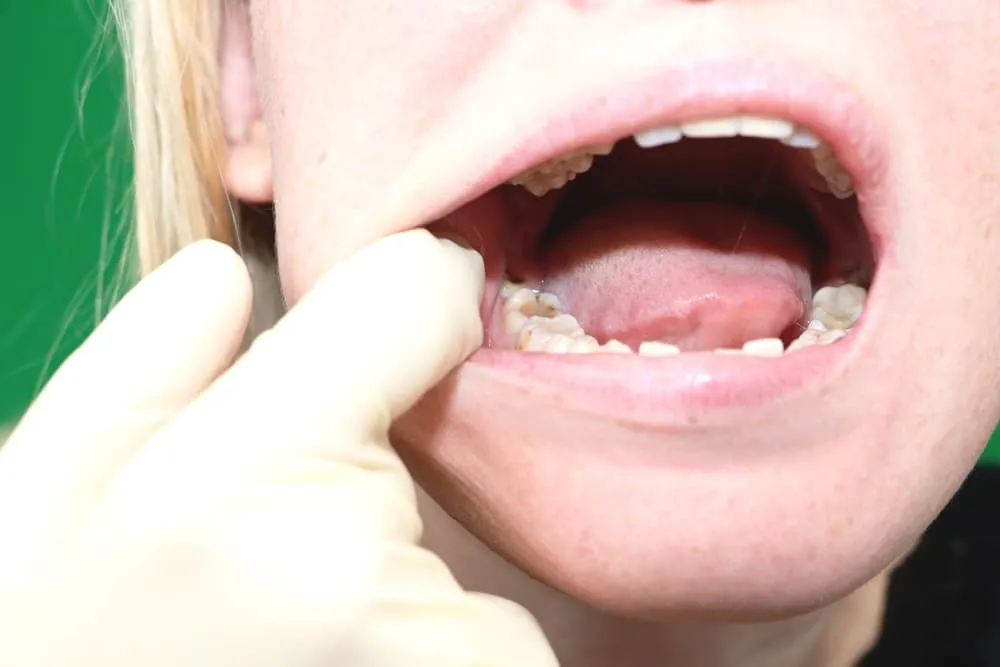

Zapalenie kieszonki dziąsłowej (pericoronitis)

Kiedy ósemka wyrzyna się tylko częściowo, nad jej koroną często tworzy się swego rodzaju "kaptur" z dziąsła. To idealne miejsce dla resztek jedzenia i bakterii, które z łatwością się tam gromadzą i są trudne do usunięcia podczas szczotkowania. W efekcie dochodzi do stanu zapalnego, zwanego pericoronitis. Dziąsło staje się czerwone, obrzęknięte i bardzo bolesne, a w niektórych przypadkach może pojawić się nawet ropna wydzielina. To sygnał, że infekcja postępuje i wymaga interwencji.

- Obrzęk i zaczerwienienie: Dziąsło wokół ósemki staje się spuchnięte i intensywnie czerwone, często nawet błyszczące. To klasyczny znak stanu zapalnego.